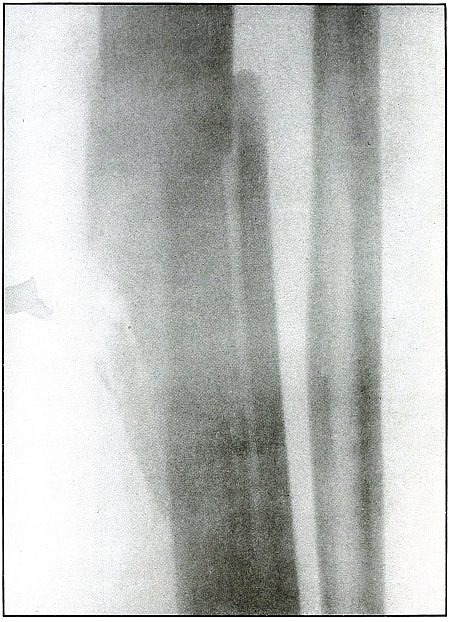

Plate 60.

_

[Pg 131]

Rifle—Plate 60.

LOWER EXTREMITY.

Gunshot Fracture of the Tibia and Fibula,

with Lodgment of the Missile.

The course of the bullet was diagonal from within outward and backward about the middle of the leg, with the impact tangential on the tibia and direct on the fibula. The bullet lies just behind the tibia.

It is apparent that the bullet has been greatly deformed and that its jacket has been badly torn from the core. The force of impact on the object from which it ricocheted must have been contributed by the velocity of short range, which reduced the striking energy so greatly that the bullet was lodged by the resistance of the tibia and fibula.

The wound was not infected, and callus formation shows that repair has begun.

The treatment in such cases, without infection, is noninterference. The lodgment of the missile need not prejudicate the prognosis, and certainly the additional damage in the search for the bullet is not warranted, except under special indications. [Pg 132]